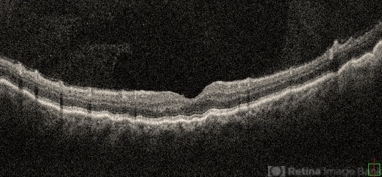

- choroidals, choroidal detachment, serous choroidal detachment

- A 52 year old male came with chief complaints of diminution of vision in RE since past 15 days. He gave history of ( RE ) cataract surgery + IOL about 2 months ago. His vision was 6/9 in RE and PL + ve, PR inaccurate in LE. His IOP was 10 mm of Hg in RE and 20 mm of Hg in LE.